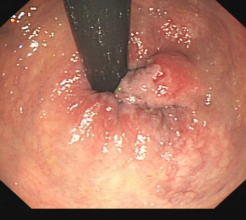

消化道早癌的病例展示(经内镜手术或活检证实):

胃角的腺癌

胃窦的微小腺癌

胃窦印戒细胞癌

十二指肠降段早癌

胃窦的腺癌 行ESD治疗

术中见较粗穿支血管,裸化后凝除,最终高效、安全的切除病灶。